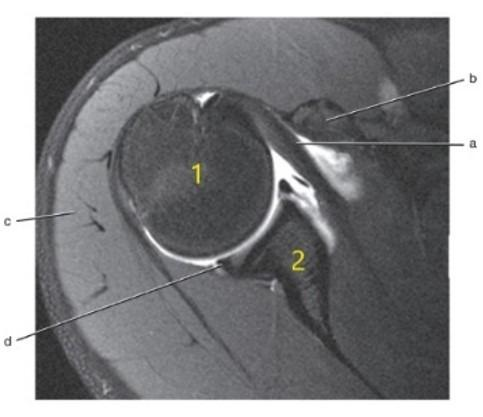

Acromion

Scapular spine

Supraspinatus tendon

Supraspinatus muscle

Superior glenoid labrum

Posterior glenoid labrum